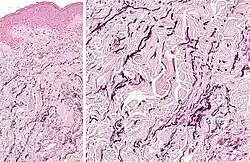

| Perforating calcific elastosis | Clumping of short elastic fibers in the dermis.[18] |

|

| Linear focal elastosis | Accumulation of fragmented elastotic material within the papillary dermis and transcutaneous elimination of elastotic fibers.[18] |

|